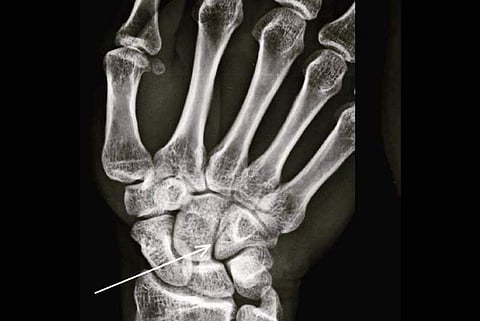

Farhan on Sunday shared a photograph of his X-Ray report on Instagram.

"When nature plays Tetris and yup, that's my first legit boxing injury... A hairline fracture on the hamate (courtesy @kongkoul ????) found among the carpal bones of the hand #nopainnogain #ToofanInTheMaking #trophycollector #weareallthesameinside," he captioned the image.